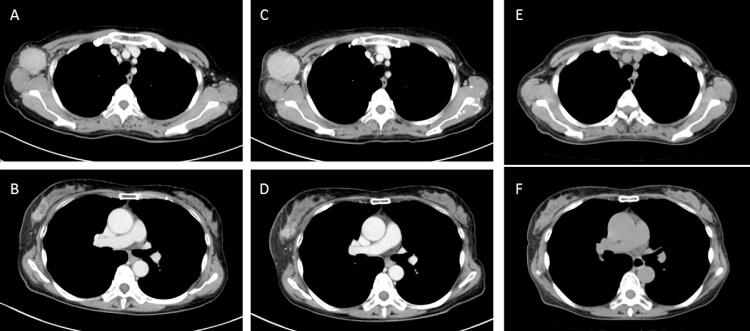

A 60-year-old woman was referred to our hospital for an axillary mass presenting three weeks ago and was diagnosed as having right locally advanced (T2N2M0, stage IIIA) triple negative breast cancer. After two courses of epirubicine and cyclophosphamide as NAC, disease progression was recognized and curative resection was considered impossible due to enlarged axillary lymph nodes showing invasion to surrounding tissue. As second-line chemotherapy, weekly paclitaxel with bevacizumab treatment was initiated and significant shrinkage was immediately obtained. A clinically complete response was diagnosed after four courses of weekly paclitaxel with bevacizumab and she underwent a right breast mastectomy with axillary lymph node dissection without major complications. Histopathological examination of surgical specimens showed no residual invasive or noninvasive disease and she was diagnosed as having a pathological complete response.

一名60岁女性因三周前出现腋窝肿块被转诊至我院,被诊断为右局部晚期(T2N2M0,ⅢA期)三阴性乳腺癌。在接受两疗程表柔比星和环磷酰胺作为NAC治疗后,疾病出现进展,由于腋窝淋巴结肿大并侵犯周围组织,认为无法进行根治性切除。作为二线化疗,开始每周使用紫杉醇联合贝伐单抗治疗,肿瘤立即出现明显缩小。在接受四疗程每周紫杉醇联合贝伐单抗治疗后,诊断为临床完全缓解,她接受了右乳乳房切除术及腋窝淋巴结清扫术,未出现重大并发症。手术标本的组织病理学检查显示无残留浸润性或非浸润性疾病,她被诊断为病理完全缓解。